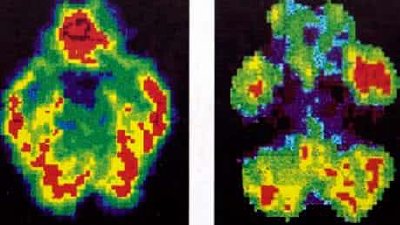

Neuroscience of Recovery Series

Current Breakthroughs in Neuroscience for Recovery

Neuroscience of Trauma Recovery